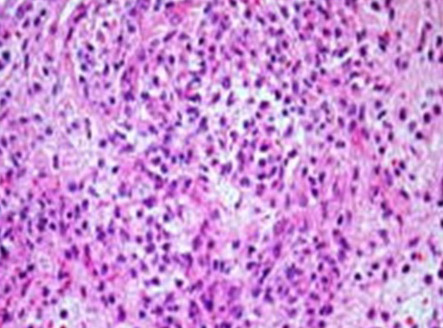

Nesta lâmina vemos um infiltrado inflamatório ativo. Nesta lâmina, corada com H/E, pode-se ao microscópio, observar as células de defesa presente, que participam dos mecanismos de defesa do hospedeiro.

Esta lâmina apresenta exemplos das céluas brancas de defesa do organismo.